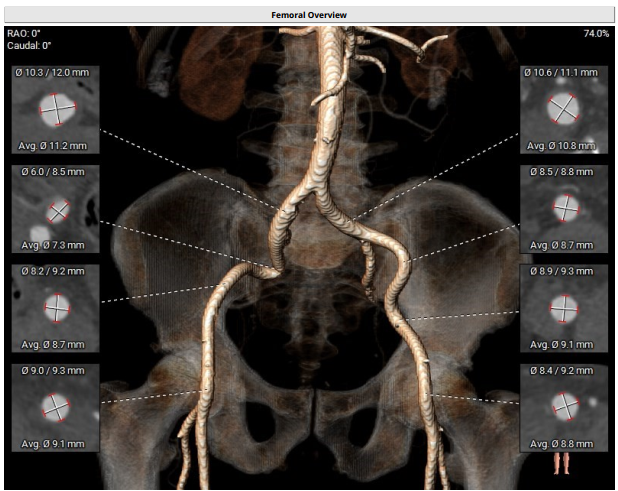

双侧股动脉血管走形稍迂曲,未见明显钙化,双侧均为低分叉;髂总动脉—降主动脉走形平直,未见明显钙化;主动脉弓部走行相对顺滑。

外周入路血管条件,主动脉弓、降主动脉及腹主动脉部分部位存在钙化。